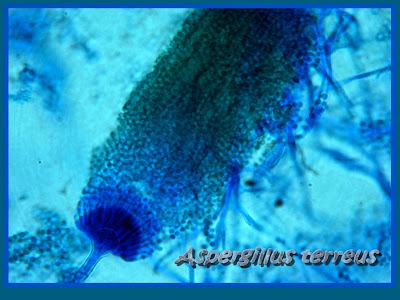

Microscopic Appearance;

-hyphae are septate and hyaline

-conidiophores are smooth walled and hyaline

-biseriate phialides, extending from the upper portion of the vesicle

-conidia form in long chains are round, smooth walled

-aleurioconida are less conspicuous and can be found on the submerged hyphae. Digging out a minute portion of the hyphae with a straight wire and squashing it under a cover slip may better reveal their presence. The appear singly as round to ovoid with truncate bases. Aleurioconidia production has been demonstrated to correlate with additional pathogenicity

Photos of 72 hour A.terreus stained with Lactophenol Cotton Blue under 400X magnification.